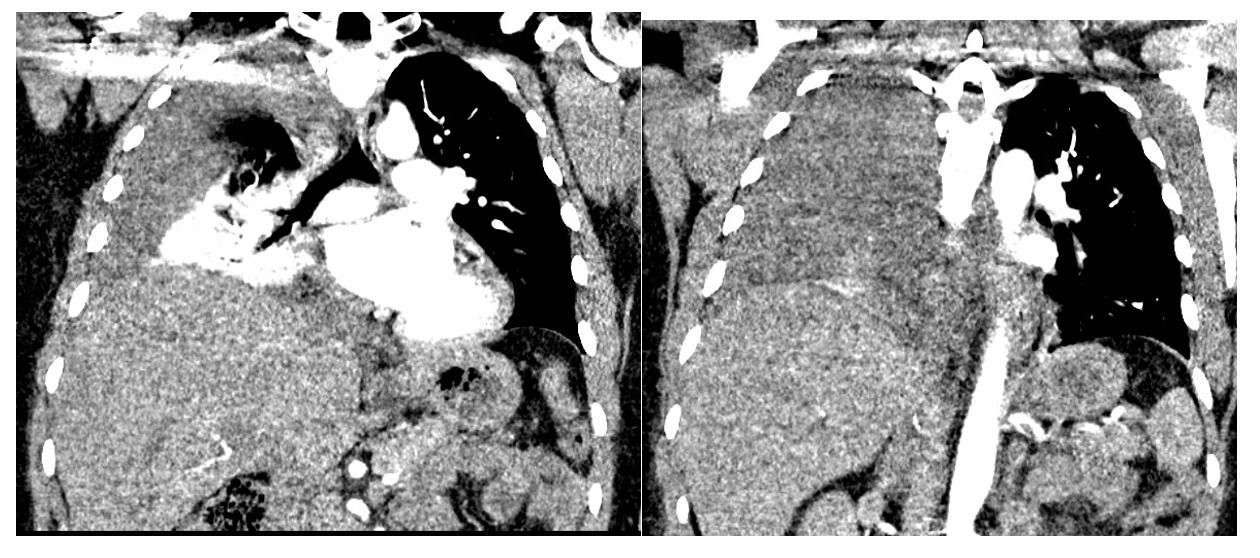

Chest CT showed large right pleural effusion consistent with a hemothorax and possible pulmonary embolism of distal vessels which was thought to be secondary to artifact after discussion with radiology. (Figure 1 and 2). Abdominal/pelvic CT showed significant heterogeneous intrauterine material and findings consistent with post-op c-section.